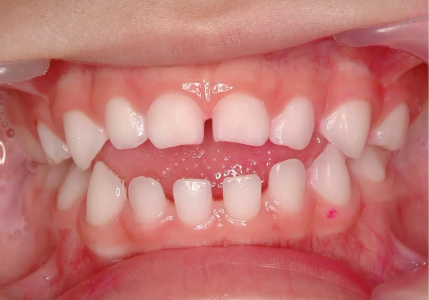

4/ Những dấu hiệu phụ huynh cần lưu ý

Nếu bé có các biểu hiện sau, cha mẹ nên đưa trẻ đi khám sớm:

- Khớp cắn ngược (răng dưới chìa ra trước)

- Khớp cắn hở (khi cắn lại vẫn hở khe giữa răng trước)

- Hàm hẹp, răng mọc chen chúc rõ rệt

Nguồn: Myfaceology

Nguồn: sarkissiandds

Nguồn: kidsdentalonline